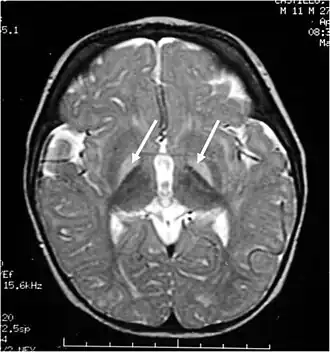

Imagerie par résonance magnétique cérébrale. Les ganglions de la base, hyperintenses en pondération T2, sont marqués d'une flèche blanche.